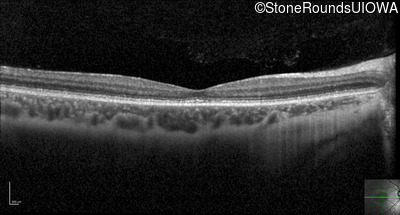

Optical Coherence Tomography - Right - 20/32 -2 sc

Exemplar / OCT Stack